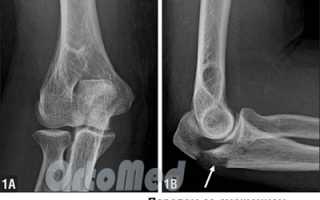

Из-за сложности травмы необходимо провести рентгенографию в двух проекциях. При закрытом переломе сопоставление костных фрагментов осуществляется вручную, с использованием местной или общей анестезии. При местном обезболивании анестетик вводится в область перелома локтевого сустава, в зоне иннервации.